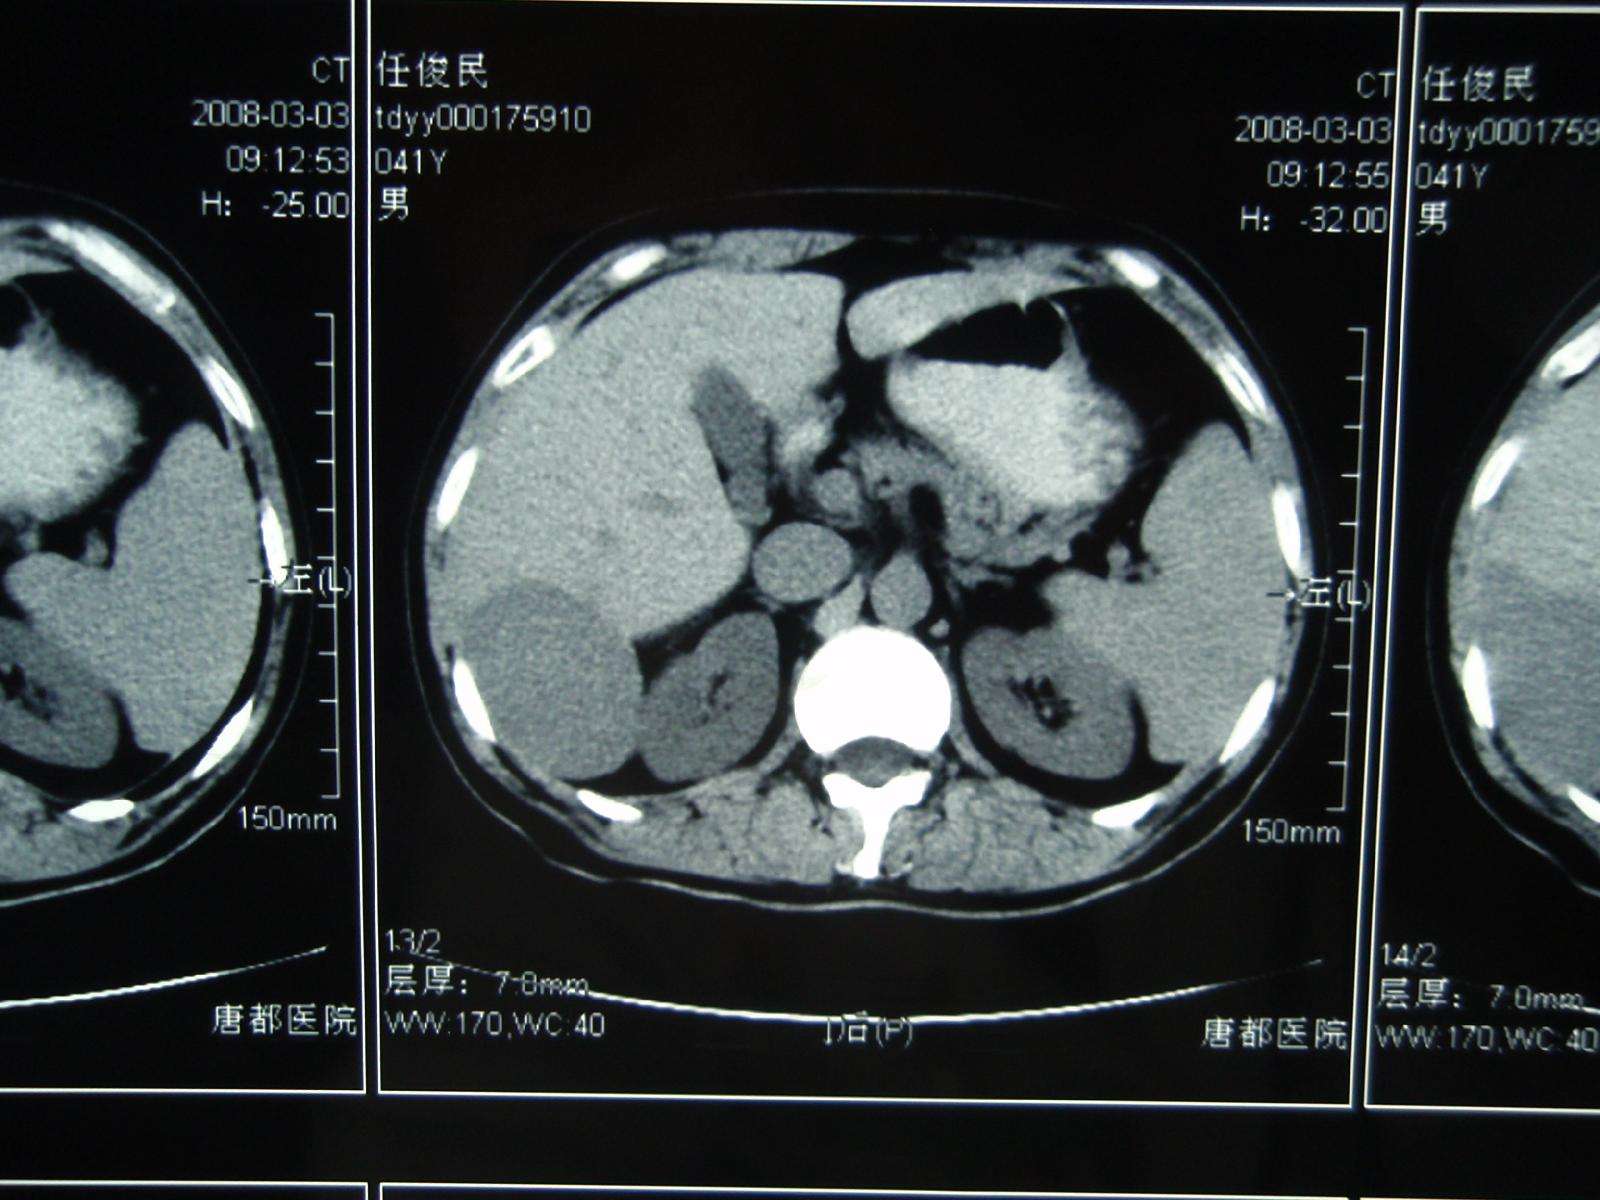

李某,女,35岁,肝区不适,2008年3月3日CT发现肝右后叶占位性病变,增强扫描确诊巨大肝血管瘤。

2008年3月5日张洪新教授做介入DSA造影明确诊断: